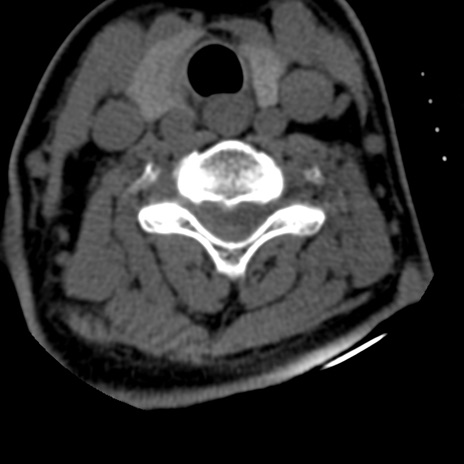

症例50 頚椎CT(横断像)

頚椎CT